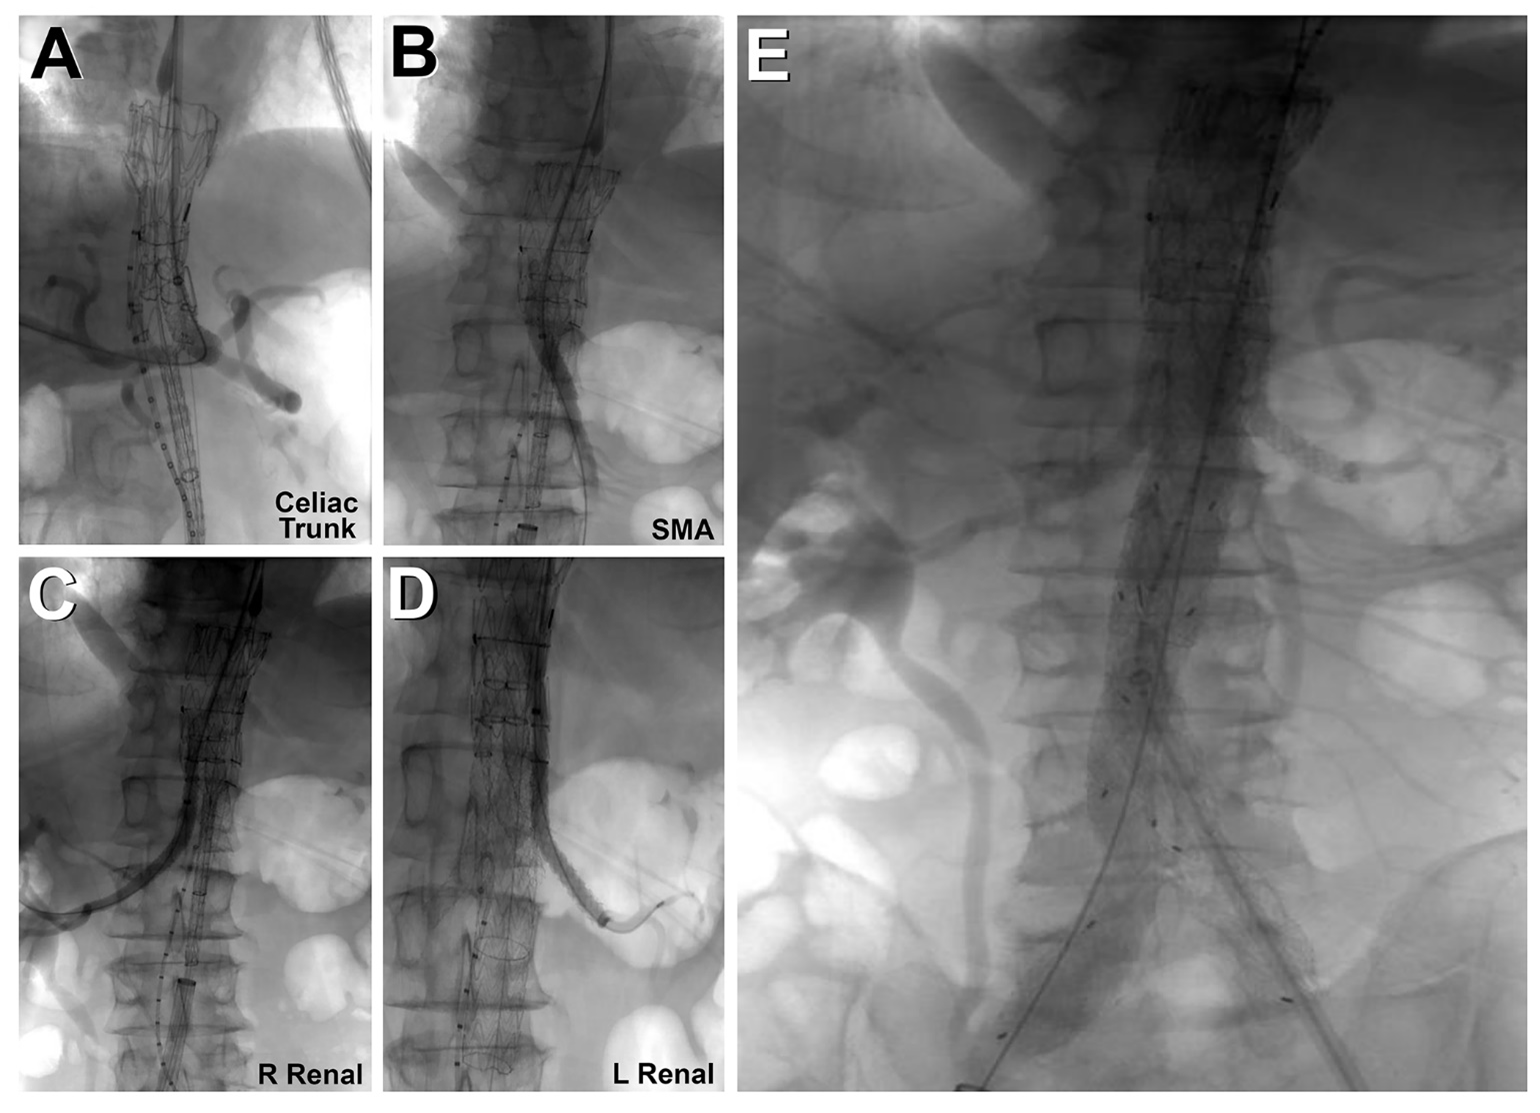

Both femoral arteries were accessed percutaneously with a Perclose device (Abbott). Left axillary artery cutdown was performed, and a 12F sheath was inserted; a 22F and a 12F sheath were deployed in the right and left femoral arteries, respectively. The TAMBE device was inserted from the right groin into the aorta and partly deployed. Using the axillary sheath, the celiac, superior mesenteric, and bilateral renal arteries were sequentially cannulated, and VIABAHN VBX stents (W. L. Gore & Associates, Inc.) were deployed. The infrarenal branch was deployed from the right groin into the TAMBE device, followed by ipsilateral limb extension from the right groin and the contralateral limb from the left groin.

CTA at completion confirmed complete exclusion of the aneurysm with preserved flow to the visceral and bilateral internal iliac arteries (Figure 3, Video 1). The total procedure time was 3 hours. The patient was discharged on the first postoperative day without complications. Two-week postoperative CTA (Video 2) confirmed patency of all target vessels and exclusion of the aneurysm sac without endoleak or migration.